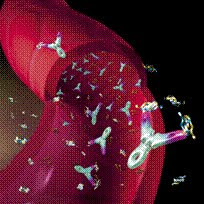

Científicos han determinado la forma en que la vitamina D3 funciona con algunas células del organismo para ayudar a limpiar el cerebro de la beta amiloidea, el principal componente de las placas que se observan en la enfermedad de Alzheimer.

Los investigadores tomaron muestras de sangre de los pacientes de Alzheimer y de personas sanas, y entonces aislaron células inmunitarias conocidas como macrófagos, que consumen la beta amiloidea y otros productos de desecho del cerebro y del cuerpo.

Hallaron que la vitamina D3 podría activar ciertas redes de señalización genética y celular, provocando así que el sistema inmunitario elimine la beta amiloidea, según el estudio que aparece en la edición del 6 de marzo de la revista Journal of Alzheimer's Disease.

Investigaciones anteriores del mismo equipo de la Universidad de California en Los Ángeles habían hallado que la terapia con vitamina D3 y con curcumina (una sustancia química que se halla en la especia cúrcuma) parecía mejorar la capacidad de los macrófagos de eliminar la beta amiloidea de los cerebros de los pacientes de Alzheimer. Sin embargo, no se sabía cómo podría funcionar.

"Este nuevo estudio ayudó a clarificar los mecanismos claves involucrados, lo que nos ayudará a comprender mejor la utilidad de la vitamina D3 y de la curcumina como terapias posibles para la enfermedad de Alzheimer", apuntó en un comunicado de prensa de la UCLA el autor del estudio, el Dr. Milan Fiala, investigador de la Facultad de Medicina David Geffen de la UCLA y del Sistema de Atención de Salud de Asuntos de Veteranos del Área Metropolitana de Los Ángeles.